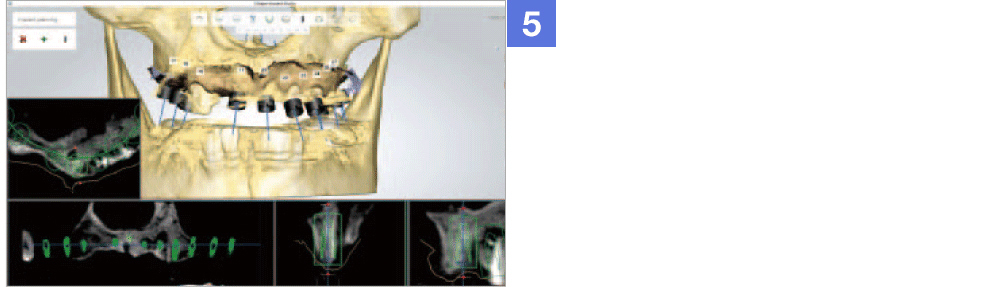

Through virtual operation procedure though 3D computer, DIO NAVI system decreases danger of implant surgery by checking patient's bone tissue and nerve position for planning the optimal surgery procedure and making customized surgical guide.

DIO NAVI surgery is planned after 3D computer simulation surgery is done, and it is up-to-date digital navigation implant surgery done with minimal incision and little pain in short time.

Not only the mock implant surgery plan that considered the occlusion and stress dispersion, but 3D simulation that can be used as a counseling material for the patient is provided. The doctor can establish a satisfactory treatment plan and with a provided surgical guide, He can operate a safe and accurate procedure.